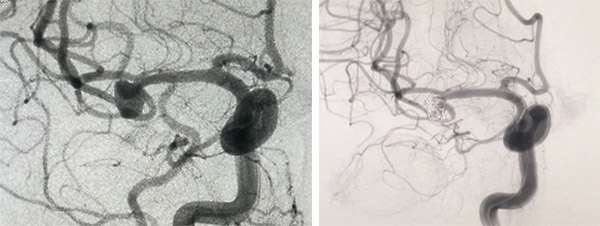

头CT查出异常,病因锁定“颅内动脉瘤” 起初,张阿姨自认为是脖子的问题,遂就诊于骨科,完善颈部CT检查提示为“颈椎退行性病变”,同时完善头CT检查提示“蛛网膜下腔出血”,骨科门诊医生感觉到问题的严重,立即请神经内科会诊,陈敬主任了解病情后马上安排医生同护士一起将张阿姨由平车接至病房。 张阿姨到病房后,陈敬主任即刻查看患者,诊断明确为“蛛网膜下腔出血,颅内动脉瘤破裂可能性大”,指导治疗,立即予止血等对症用药,同时急检抽血化验,完善头颈部CTA检查提示“右侧大脑中动脉近M2段见结节样凸起,大小约6mm×6mm”,病因明确:右侧大脑中动脉动脉瘤破裂伴蛛网膜下腔出血。对于颅内动脉瘤破裂出血,应尽早通过介入治疗进行干预,以降低再出血风险,所以立即联系介入科,共同商讨手术事宜。 造影、动脉瘤栓塞、支架……多学科协作成功“拆弹” 经过周密的讨论,制定手术方案。张阿姨于入院当晚在神经中心、导管室、麻醉科、介入科共同努力下完成脑动脉造影术、经导管颅内动脉瘤栓塞术、颅内血管支架经皮置入术,术中发现右侧大脑中动脉动脉瘤的瘤体分叉处可见多个远端分支血管,在栓塞动脉瘤时要保留远端血管功能,以防栓塞后出现神经功能缺损,在介入科医生精湛的医术下隐藏在患者脑中的“炸弹”被成功拆除。两个半小时的手术非常顺利,术后患者镇静状态,转入CCU心脏重症监护病房,密切观察。次日凌晨1时30分,患者意识清醒后拔除气管插管,自诉头颈部疼痛明显减轻。术后给予抑酸、脱水、缓解血管痉挛、抑制血小板聚集、调脂等常规治疗。 目前张阿姨已离开CCU心脏重症监护病房,转回神经科普通病房继续治疗,观察病情。 警示:头痛、颈痛别马虎,这是神经科的危重症! 蛛网膜下腔出血为神经科危重症,总体预后较差,其病死率高达45%,存活者亦有很高的致残率。突发的迅速达到顶峰的剧烈霹雳样头痛应引起接诊医师对蛛网膜下腔出血(SAH)的高度怀疑,大约80%的SAH的患者会主诉“一生中从未有过的头痛”。SAH患者还可伴或不伴恶心、呕吐、颈项强直、短暂意识丧失、局灶性神经体征等。SAH最常见的病因为颅内动脉瘤(约占75%-80%)和血管畸形(约占10%),对于大部分破裂动脉瘤患者,应尽早通过介入治疗或开颅手术对动脉瘤进行干预(发病72 h内),以降低再出血风险。伴颅内压增高患者应用甘露醇脱水治疗,可予地塞米松减轻脑水肿,合并脑室内出血或脑积水者可行脑室外引流;需维持电解质平衡,特别注意低血钠,防治血管痉挛。 张阿姨入院10余小时即明确诊断并完成介入治疗,得益于沈阳市第十人民医院(沈阳市胸科医院)多学科的默契配合,才能在最短的时间内解除颅内动脉瘤再破裂的最大的危险。 在这里专家提醒:冬季天气寒冷,是脑心血管疾病的高发期,如果出现头晕、头痛、颈部疼痛、心悸胸闷等情况,一定要及时就诊。 供稿:神经内科 神经内科 科室简介: 沈阳市第十人民医院(沈阳市胸科医院)神经中心内科组成立于2014年3月,是集医疗、科研、教学于一体的临床科室,是中国卒中中心联盟单位、红手环志愿者单位、“中风120”辽宁特别行动组成员,是沈阳市急性脑卒中医疗救治第一批定点医院。科室对神经系统疾病的诊治具有丰富的临床诊疗经验,诊疗范围: 1.脑血管病:急性缺血性脑血管病的静脉溶栓、动脉取栓;颅内外动脉狭窄的支架植入;脑出血的诊治;脑静脉系统血栓形成的诊治;脑血管病的二级预防;脑血管病危险因素的筛查、一级预防等。 2.神经系统变性疾病:阿尔茨海默病、帕金森病、路易体痴呆、进行性核上性麻痹、多系统萎缩、运动神经元病、痴呆的鉴别诊断等。 3.神经系统脱髓鞘疾病:多发性硬化、视神经脊髓炎谱系疾病、吉兰-巴雷综合征等。 4.神经系统感染性疾病:病毒性脑炎、脑膜炎、脊髓炎、脑囊虫病等。 5.神经-肌肉接头和肌肉疾病:重症肌无力、多发性肌炎、线粒体肌病和脑肌病等。 5.神经系统的其他常见病:头晕、头痛、眩晕、面瘫、三叉神经痛、癫痫、睡眠障碍等。 6.其他系统疾病的神经系统并发症:副肿瘤综合征、糖尿病性多发性周围神经病、糖尿病性单神经病、酒精中毒性相关神经病等。 本着"患者至上、质量为本"的原则,全体医护人员将团结协作、不断进取,对每位患者做到热情接待、合理检查、耐心讲解、规范诊疗,力求以最少的费用,创最佳的疗效。 地址:1号楼十一层 联系电话:024-88323438转8225